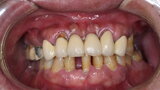

Compromised maxillary dentition treated with Straumann Pro Arch and a digital workflow